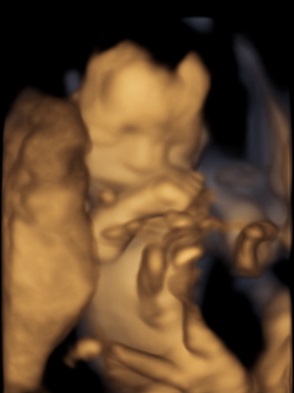

On May 27, we went for another ultrasound appointment. It was THE appointment - the day we could finally know the gender of our little human.

The sonographer of THE day sucked big time though. Bleh. I made sure to complain the next appointment and I had this 4D print as compensation.

LG said our baby girl looks like me. I'm not sold on that, but I was hoping otherwise. :X

So the shopping for clothes officially started. Pretty bows and lace, here I come!